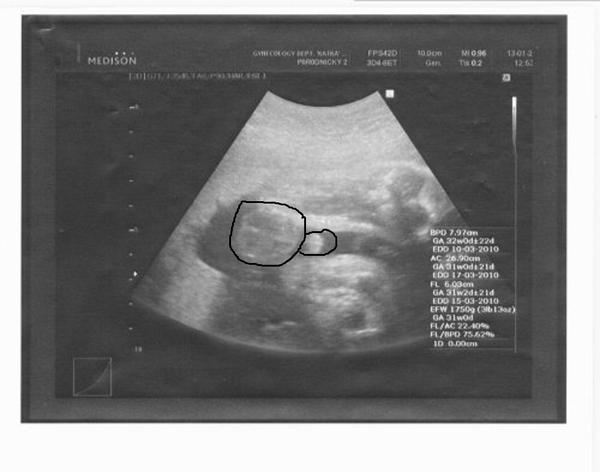

Ahoj maminky a budoucí maminky 😉 Prosím, poradila byste mi některá, co vidíte na fotce z ultrazvuku ve 20. týdnu za pohlaví? Určitě jste foteček viděly už mraky, proto vás žádám o radu...Nechci nikoho ovlivnit, proto svůj tip řeknu později 🙂 Děkuju moc!!!

Tak já tipuju kluka, pupečník by asi u tělíčka nebyl tak široký, ne?

No teda já nevím, ale to je naprosto jasný kluk ne?

...vidím to spíše na kluka

Našla jsem foto holčičky. Tady není pupečník vůbec vidět, takže u tebe to bude asi pindík.

Já mám dva kluky a na obou UTZ jsem je rozeznala ještě než to stačil doktor říct. A toto mi přijde taky jako klučík! 😉

Mam uplne stejnou fotku, je to kluk jak buk...😉

to je jasný pinďourek no 🙂

Tak abych konečně vnesla do této diskuze světlo, dnes mi bylo potvrzeno, že to bude chlapeček 🙂 Pindík i s pytlíkem se na monitoru nedaly přehlédnout, to by poznal snad i slepý 😀 A tentokrát říkal i dr. že by za chlapečka dal klidně ruku do ohně, takže je to venku 🙂 Děkuju moc všem za názory, bylo to napínavé!! 😉